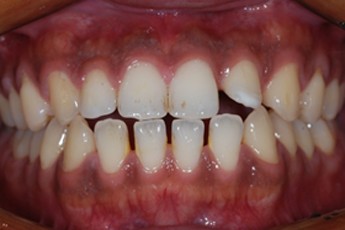

BEFORE & AFTER

- 덧니교정